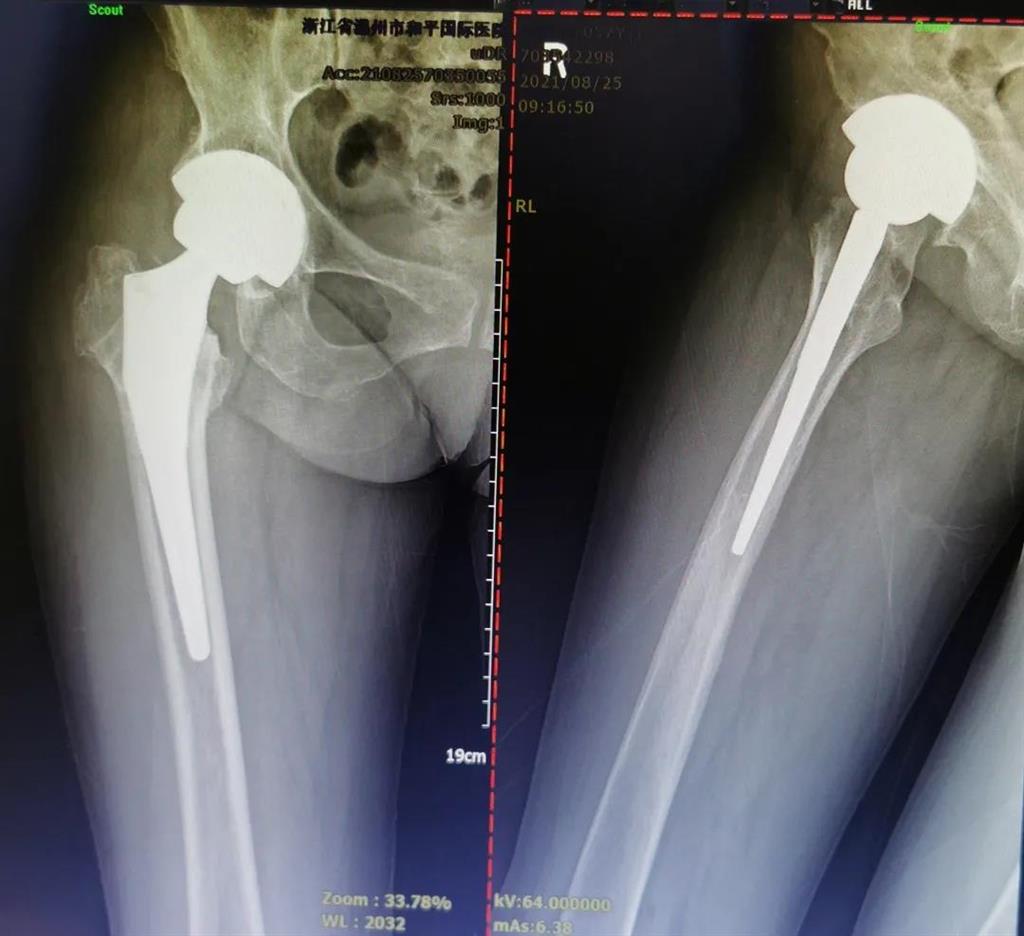

手術(shù)很成功!李女士術(shù)后第二天便可下地進(jìn)行簡(jiǎn)單的鍛煉了。

兩個(gè)月后,李女士的腿已與常人無異,苦纏2年有余的病痛,終于徹底消散。

(△做完“右股骨頸全髖關(guān)節(jié)置換術(shù)”后的影像)